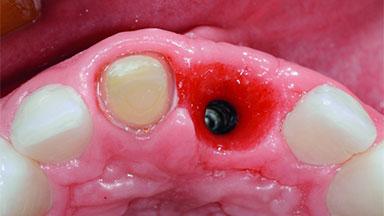

Replacement of an Ankylosed Upper Left Central Incisor: Bone Augmentation and Socket Grafting, Late Placement of an RC Bone Level Implant

A 15-year-old male patient was referred to us by his pediatric dentist in June 2004 for evaluation of treatment options for his failing tooth 21. The patient had recently seen an endodontist for internal bleaching and been advised that there had been significant resorption and ankylosis. The patient’s mother was concerned because the tooth appeared shorter than the adjacent one. His past dental history was significant for trauma (September 2001), where the tooth had been avulsed and reimplanted. Teeth 11 and 21 had been endodontically treated.

Bone Volume Deficient horizontally, requiring prior grafting